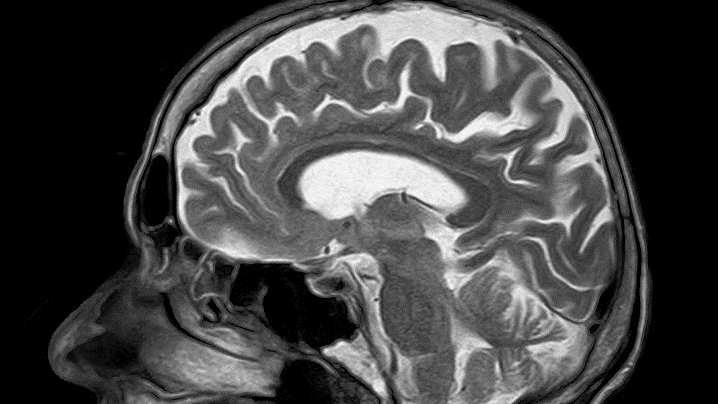

80 milijuna ljudi preživjelo je moždani udar diljem svijeta, dok 50 milijuna preživjelih živi s nekim oblikom trajne invalidnosti. Predviđanja su da će ove godine 14,5 milijuna ljudi doživjeti moždani udar, a 5,5 milijuna ljudi će umrijeti od posljedica moždanog udara. Moždani udar među najčešćim je uzrocima smrti, može se dogoditi neočekivano i ne bira životnu dob. U 85% slučajeva uzrokovan je začepljenjem krvne žile ugruškom. Tada se oštećenje mozga i invaliditet mogu umanjiti/spriječiti lijekovima (tromboliza) ili mehaničkim uklanjanjem ugruška (trombektomija).

Važno je prepoznati simptome moždanog udara te se što hitnije javiti liječniku kako bi se na vrijeme poduzele odgovarajuće dijagnostičke i terapijske mjere. Pravovremenim početkom liječenja (što prije, najbolje unutar prva tri sata), takva se stanja mogu izliječiti.